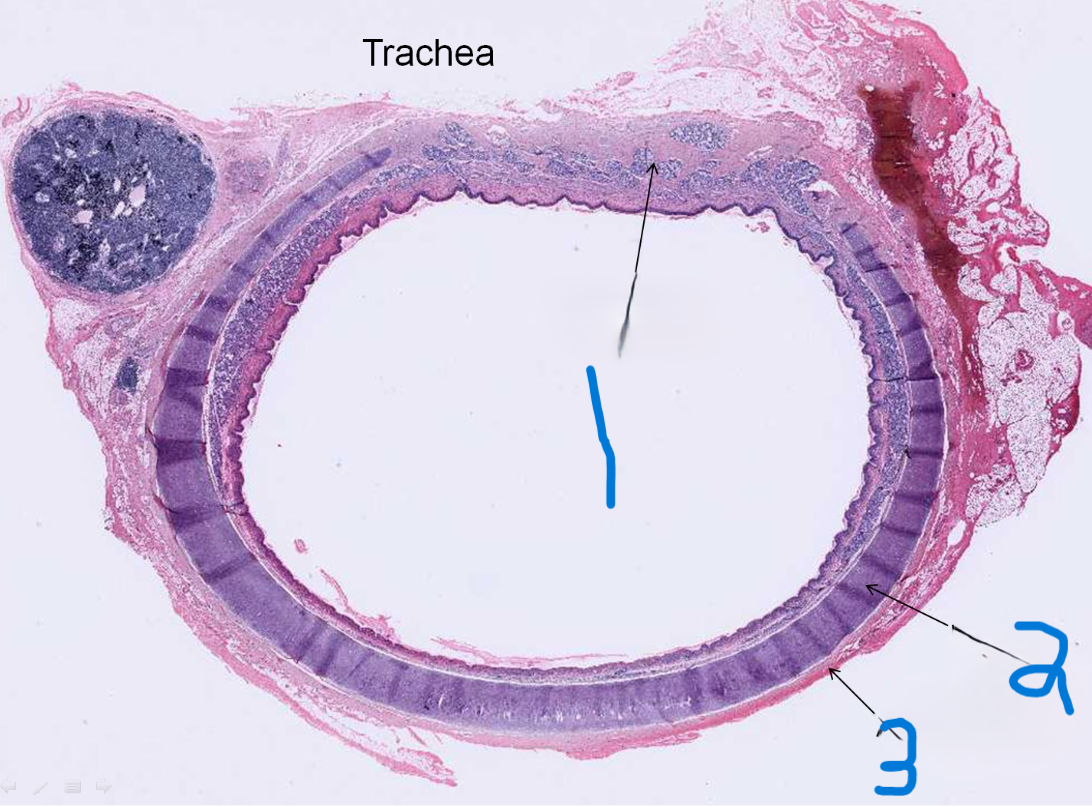

What is depicted by #1

Hyaline cartilage

What is depicted by #2

Adventitia

What is depicted by #3